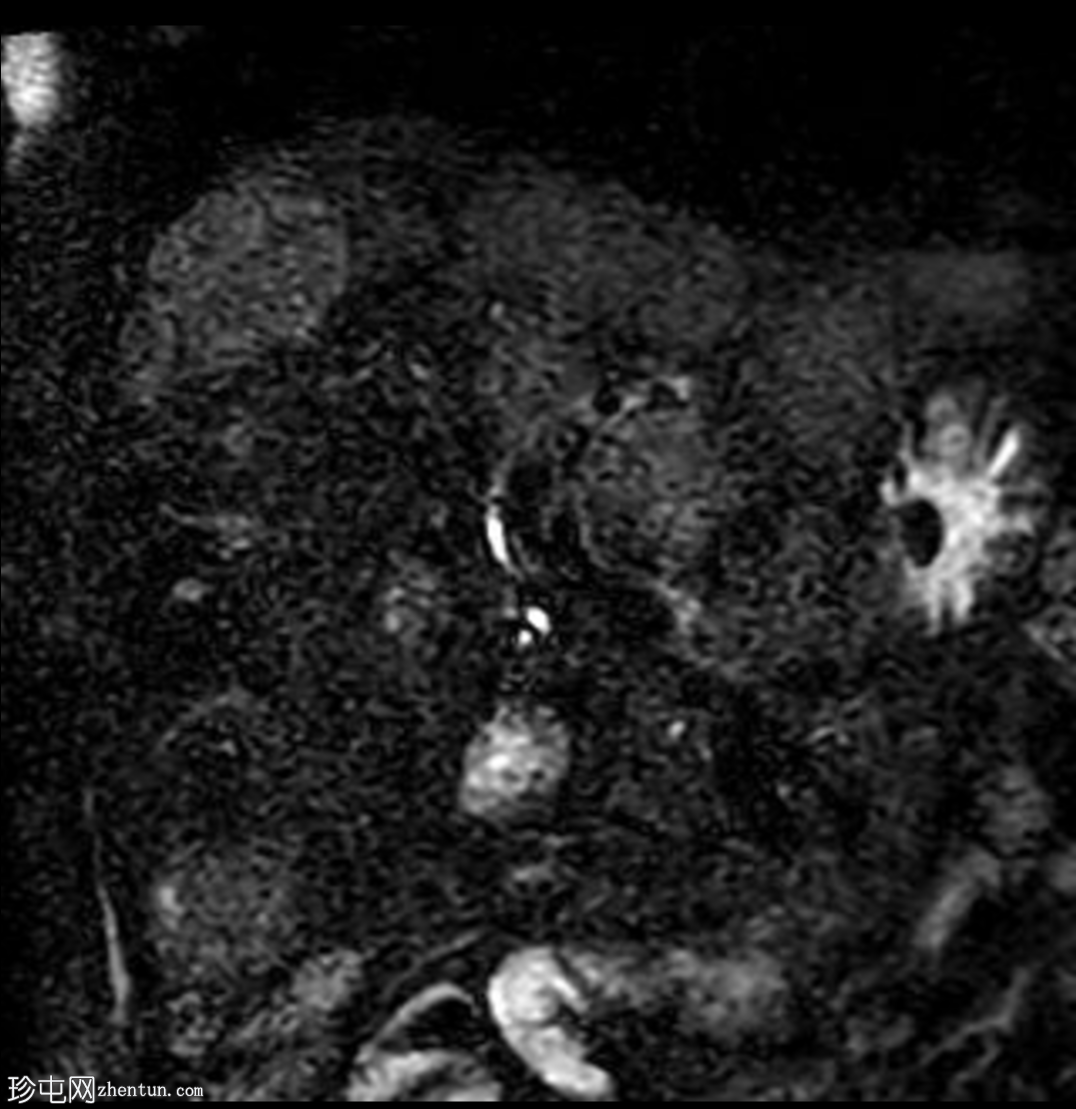

冠状位

MRCP

肝脏多发病灶,其中数个病灶呈中心T2高信号。

磁共振胰胆管造影(MRCP)显示肝转移灶处存在多处短段胆管狭窄和闭塞,上游胆管扩张,提示

肿瘤

直接压迫/浸润。

肝总管(CHD)和胆总管(CBD)通畅,管径正常。

无胆总管结石。

肝转移灶中心T2高信号最可能是由于肿瘤快速生长导致的中心坏死。

与转移性胆管癌相比,恶性胆道梗阻在胆管癌中更为常见。